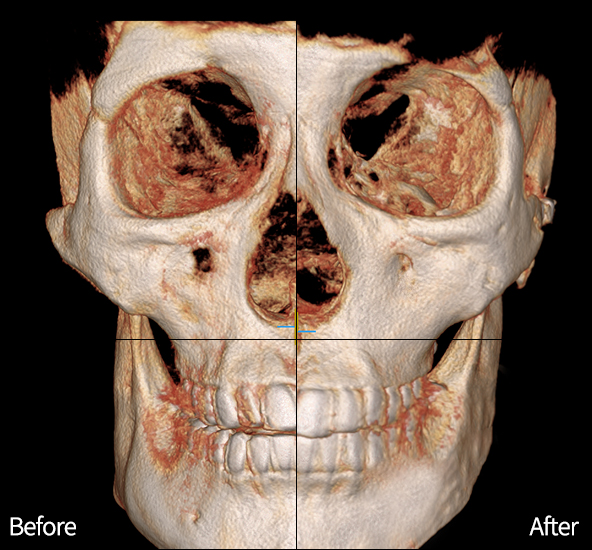

#완전고정 광대축소

넓은 옆광대를 줄여

슬림한 얼굴형으로 개선

입안 절개, 뼈·피부 미세분리

흉터, 볼처짐 예방

아이디가 개발한 티타늄 핀으로

튼튼하게 완전고정

#곡선절제 사각턱축소

턱의 볼륨 부위를 곡선 절제해

매끄러워지는 턱 라인!

신경손상 걱정 없도록

개인별 신경 주행경로 확인!

커브는 부드럽게!

정면 · 측면 어디서봐도 매끄럽게 예뻐지고

뼈까지 예뻐지는 id 윤곽2종 ♥